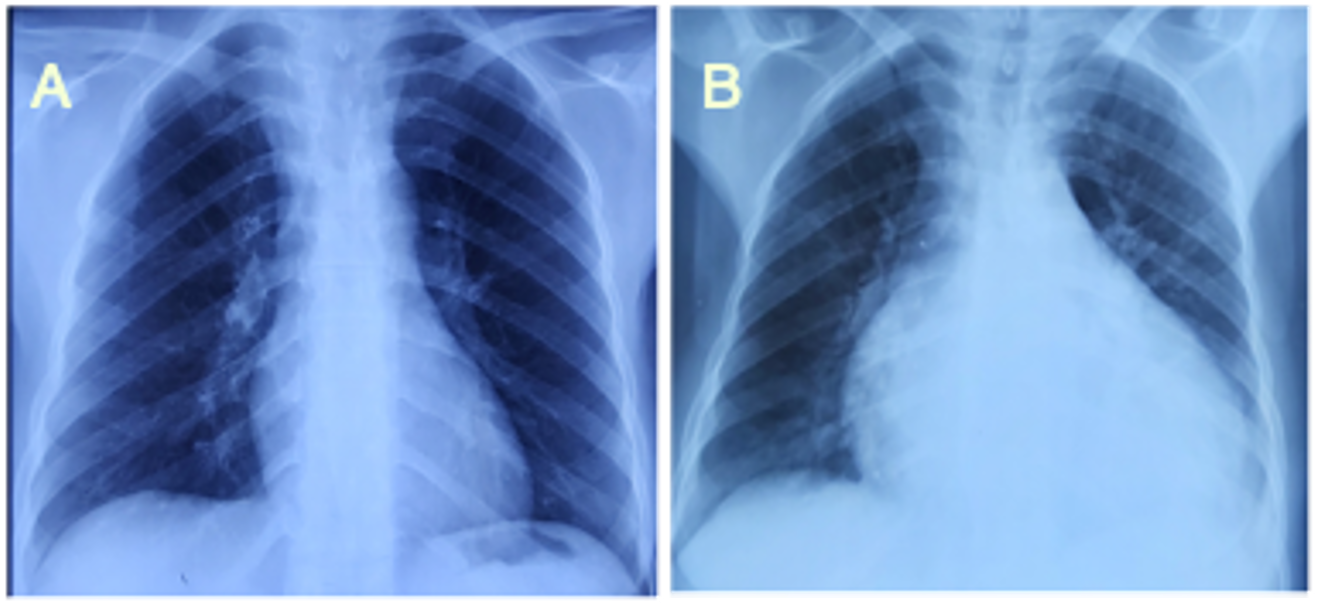

A male patient aged 23, on automated peritoneal dialysis since 2021 (APD: total volume 10 L, 4 cycles of 2 h, injection volume 2 L, final stasis 1 L, concentrations 2.27%). The measured dialysis dose was a total Kt/V of 1.35 and a WCCr of 38 L/week/1.73 m2, nPCR at 0.85. One week prior to admission, the patient presented with non-radiating retrosternal chest pain with dyspnea. An ECG and chest X-ray were performed, which came back unremarkable. With worsening chest pain and dyspnea, the patient was admitted to the emergency department. Clinical examination revealed tachycardia at 115 bpm, BP 140/90 mmHg, apyrexia, decreased heart sounds, orthopnea, SpO2 of 95% on room air, no crepitus rales, and no signs of right heart failure. ECG showed diffuse microvoltage. Chest X-ray revealed cardiomegaly (ICT 0.7) with hilar overload (Figure 3.). TTE showed a large circumferential pericardial effusion at 23 mm without collapse, with fibrin deposits, dilated IVC, and 50% LVEF (Figure 4.). A biological inflammatory syndrome was present, with CRP of 160 mg/L without hyperleukocytosis, and negative troponin 28 ng/dL. The patient underwent emergency pericardiocentesis, yielding 500 mL of hematic, exudate fluid (protein 56 g/L). Cytobacteriological examination, BK testing, and GeneXpert in the puncture fluid were negative, with no cells suspected of malignancy on pathology.

Figure 4.Subcutaneous TTE section showing a large pericardial effusion with fibrin